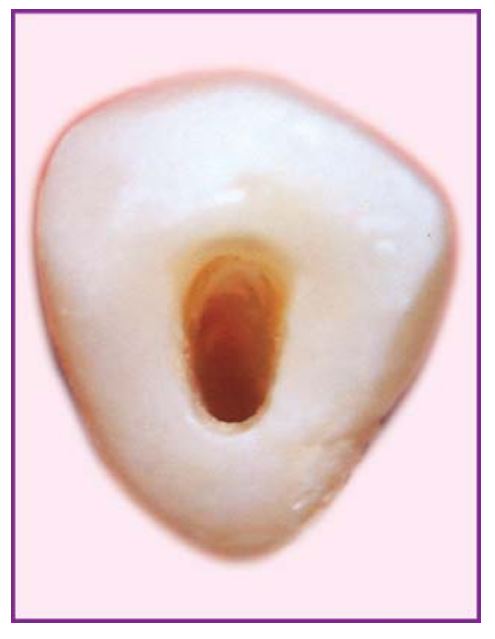

Khi nhìn từ mặt nhai hoặc mặt trong phải thấy rõ tất cả miệng ống tủy (H5.1 a,b).

Răng 4 hàm trên (H5.9).

Răng này có rất nhiều biến thể khác nhau về số lượng cũng như hình dạng ống tủy. Thường có 2 ống tủy, ngoài và trong. Buồng tủy rộng theo chiều ngoài trong với 2 sừng tủy riêng biệt. Xoang tủy cũng có hình dạng tương tự, hình oval và rộng theo chiều ngoài trong. Xoang tủy đôi khi phải mở rộng đến múi răng khi ống tủy nằm bên dưới đỉnh múi.